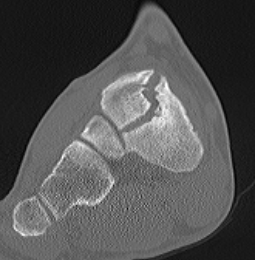

CT

Minimally displaced navicular stress fracture

Displaced navicular stress fracture